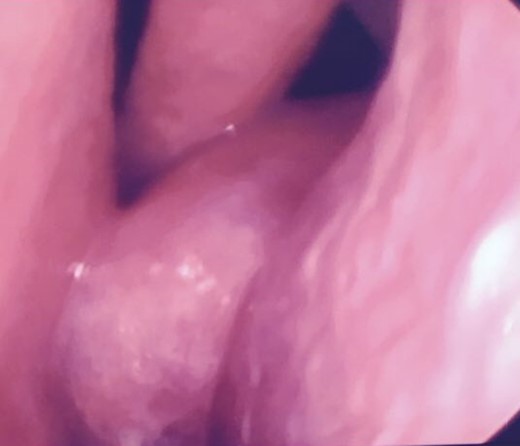

Anterior rhinoscopy and nasofibroscopique revealed pale polypoidal masses in both nasal cavities, arising from each middle meatus and extending to the nasopharynx (Fig. 1).